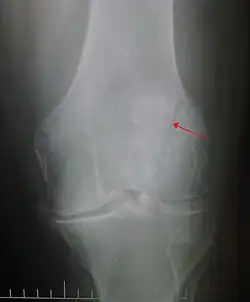

Patella fracture

A patella fracture is a break of the kneecap.[1] Symptoms include pain, swelling, and bruising to the front of the knee.[1] A person may also be unable to walk.[1] Complications may include injury to the tibia, femur, or knee ligaments.[2]

It typically results from a hard blow to the front of the knee or falling on the knee.[1]The patella can also be fractured indirectly. For example, a sudden contraction of the quadriceps muscle in the knee can pull apart the patella.[1]Diagnosis is based on symptoms and confirmed with X-rays.[3] In children an MRI may be required.[3]

The patella can break in various ways depending on the way it is injured, and into two or more pieces.[1] Types include transverse, the most common, with one fracture line;[5] marginal; osteochondral; and the rare vertical type, or stellate, where a direct compression force gives rise to a comminuted pattern.[5][7] Patella fractures can be further classified as displaced, where the broken ends of bone do not line up correctly and separate by more than 2mm, or undisplaced and stable where pieces of bone remain in contact with each other.[1][7] If fragments of patella bone stick out from the skin it is known as an open patella fracture, and closed if the overlying skin is intact.[1]